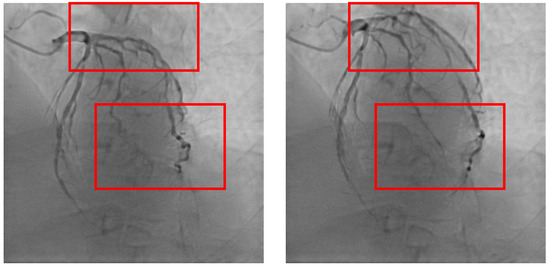

4.2. Dataset